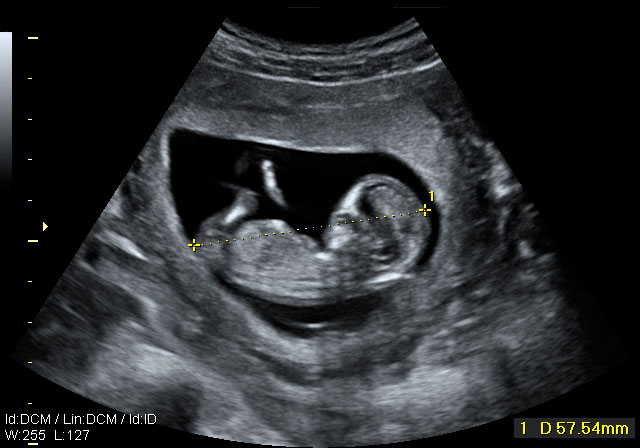

Ecografía 4D de la semana 12: Feto moviéndose de perfil

La ecografía 4D muestra al bebé moviéndose a sus anchas en el útero materno. Este plano de perfil muestra brazos, piernas y cordón umbilical en movimiento constante, lo que es es signo de vitalidad fetal. Las estructuras básicas de un feto de 12 semanas de gestación se parecen mucho a las de un bebé recién nacido; es ya todo un niño, aunque le falten unos seis meses aproximadamente para ver la luz.

Ecografía 4D: feto de 12 semanas moviéndose de perfil